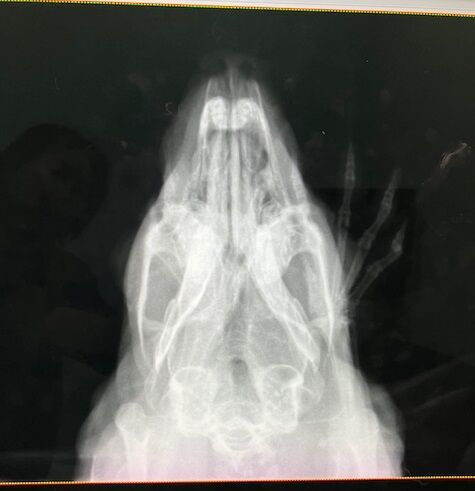

12月4日、ドナちゃん避妊手術しました。

術前の血液検査、レントゲン、いずれも問題ありません。

※白血球の上昇などはストレス起因と判断できるレベル、と、

血小板は機械の誤作動による、顕微鏡で別途確認済

奥歯も問題なし。